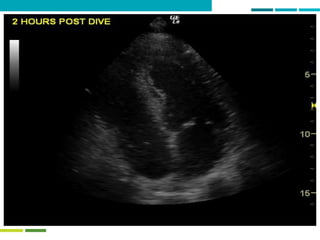

Two mechanisms of bubble formation –

with a twist!

BUBBLE FORMATION

Dissolved gas Pulmonary barotrauma

Venous blood Arterial bloodTissues

Patent foramen ovale + other shunts